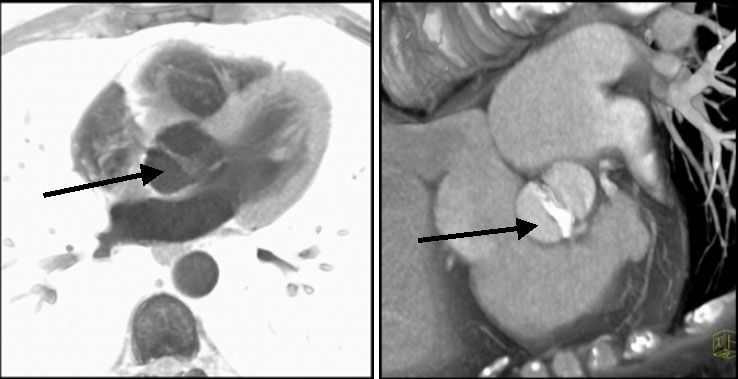

С помощью МСКТ описана возможность визуализации бикуспидального аортального клапана (рис № 20,21), выявление вегетаций на аортальном клапане при инфекционном эндокардите [43] (рис № 24).

Известно, что пациенты с бикуспидальным аортальным клапаном имеют высокий риск развития аневризмы восходящего отдела аорты и ее диссекции, поэтому у таких пациентов важна точная диагностика поражения, для проведения своевременной хирургической коррекции данной патологии.

![]() |

| Рис.20-21. Слева - бикуспидальный аортальный клапан (стрелка). Справа-кальцинированный бикуспидальный аортальный клапан (стрелка). |

| Рис.22-23. Кальциноз аортального клапана (стрелка). Справа протез аортального клапана. |